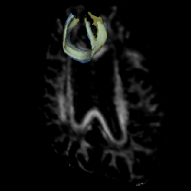

Fig. 4 provides a visualization of our segmentation result. It overlaps with the reference standard in (a) and (c) for FMI and right CST, respectively. The mean test DC of FMI is 0.66 (SD 0.06), that of CST is 0.77 (SD 0.03).

Fig. 4 (b)(d) provide its overlaps with segmented rescan, which was registered by rigidly aligning the FA images. Table 1 gives the reproducibility statistics. Typically, a indicates “substantial” agreement between raters, and a for “almost perfect” [16]. Our mean for FMI longitudinal-segmentations achieved 0.74 and 0.80 for CST. The and show that our method has better reproducibility than reference. Moreover, there was no difference in our longitudinal-measures (FA, MD, volume, paired t-test, ). Our mean FA and MD are consistent with that of the reference. These results show that our method is applicable in longitudinal analysis of WM microstructure.

Fig. 4 provides subject-wise reproducibility in determining diffusion measures. The Bland-Altman plots show that almost all differences are within the limits of agreement and the mean of which is close to zero, indicating no consistent bias in longitudinal-measures. Additionally, Fig. 4 (right) shows that the MD is a discriminative feature for FMI and CST tract.